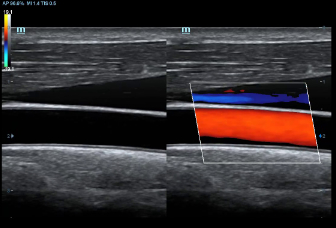

DC-70 Exp

–Ш–љ—Б—В—А—Г–Љ–µ–љ—В –і–ї—П –≤—Л—Б–Њ–Ї–Њ–Ї–∞—З–µ—Б—В–≤–µ–љ–љ–Њ–є –і–Є–∞–≥–љ–Њ—Б—В–Є–Ї–Є

X-Insight вАУ —Н—В–Њ –Њ—В–ї–Є—З–љ–Њ–µ —А–µ—И–µ–љ–Є–µ –і–ї—П –Њ–њ—А–µ–і–µ–ї–µ–љ–Є—П –љ–Њ–≤—Л—Е –≤–Њ–Ј–Љ–Њ–ґ–љ–Њ—Б—В–µ–є.

–°–Њ–≤–Љ–µ—Б—В–љ–Њ —Б —Б–Њ–≤—А–µ–Љ–µ–љ–љ—Л–Љ–Є —Г–ї—М—В—А–∞–Ј–≤—Г–Ї–Њ–≤—Л–Љ–Є —В–µ—Е–љ–Њ–ї–Њ–≥–Є—П–Љ–Є –љ–Њ–≤–Њ–µ —А–µ—И–µ–љ–Є–µ –Њ—В Mindray –њ—А–µ–Њ–±—А–∞–Ј—Г–µ—В –∞–Ї—В—Г–∞–ї—М–љ—Л–µ –Ј–∞–і–∞—З–Є –Ї–ї–Є–µ–љ—В–Њ–≤ –≤ –Ї–ї–Є–љ–Є—З–µ—Б–Ї–Є–µ –њ–Њ—В—А–µ–±–љ–Њ—Б—В–Є.

–°–Є—Б—В–µ–Љ–∞ DC-70 Exp —Б X-Insight –њ–Њ–Љ–Њ–≥–∞–µ—В —Г–њ—А–∞–≤–ї—П—В—М –њ–Њ–≤—Б–µ–і–љ–µ–≤–љ–Њ–є –Ї–ї–Є–љ–Є—З–µ—Б–Ї–Њ–є –њ—А–∞–Ї—В–Є–Ї–Њ–є —Б –ї–µ–≥–Ї–Њ—Б—В—М—О –Є —Г–≤–µ—А–µ–љ–љ–Њ—Б—В—М—О.

–Ю—Б–љ–Њ–≤—Л–≤–∞—П—Б—М –љ–∞ –≥–ї—Г–±–Њ–Ї–Њ–Љ –њ–Њ–љ–Є–Љ–∞–љ–Є–Є –њ–Њ—В—А–µ–±–љ–Њ—Б—В–µ–є –Ї–ї–Є–µ–љ—В–Њ–≤, –Ї–Њ–Љ–њ–∞–љ–Є—П Mindray —А–∞–Ј—А–∞–±–Њ—В–∞–ї–∞ —Б–Є—Б—В–µ–Љ—Г DC-70 Exp —Б X-Insight, —З—В–Њ–±—Л –Њ–±–µ—Б–њ–µ—З–Є—В—М eXpress Clarity, eXceptional Intelligence, eXceeding Experience.